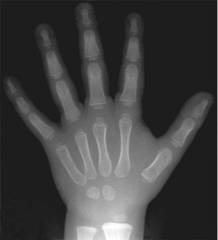

У детей рентгенологическое изображение скелета отличается рядом особенностей. Это связано с наличием росткового хряща и ядер окостенения. Рентгенологическая картина суставов у детей зависит от возраста ребенка. Примером отличий рентгенограмм скелета ребенка от рентгенограммы взрослого человека является снимок костей кисти трехлетнего ребенка.

Рис. 9. Рентгенограмма кисти 3-летнего ребенка (норма). Видны широкие зоны роста и ядра окостенения

Из всех компонентов опорно-двигательной системы естественной рентгеновской контрастностью обладает только костная ткань. Хрящевая ткань "проницаема" для рентгеновских лучей. Поэтому на рентгенограммах костей и суставов детей не получает отображение целый ряд анатомических образований. Например: на первом году жизни это эпифизы трубчатых костей, кости запястья и предплюсны, в более старшем возрасте - апофизы и бугристости костей. Рентгенограммы отображают морфологию кости - ее форму, очертания и внутреннее строение. Рентгеновское излучение поглощается в основном плотными частями кости, содержащими соли кальция, т.е. костными балками. Надкостница, эндост, костный мозг, сосуды, нервы, суставной и ростковый хрящ не дают в норме на обычной рентгенограмме различимой тени на снимках. Такую возможность врачам предоставляют современные методы исследования, чаще в комплексном использовании: КТ, МРТ, сонография. На обычных рентгенограммах о них можно судить по косвенным признакам - состоянии костных балок, кортикального слоя кости, суставной щели. В кортикальном слое балки расположены настолько близко друг к другу, что на снимках он представляется сплошным массивом. В губчатом веществе балки находятся на некотором расстоянии друг от друга - они разделены пространствами, заполненными костным мозгом.